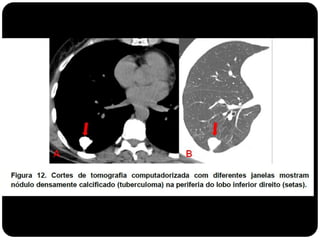

Granuloma de TB